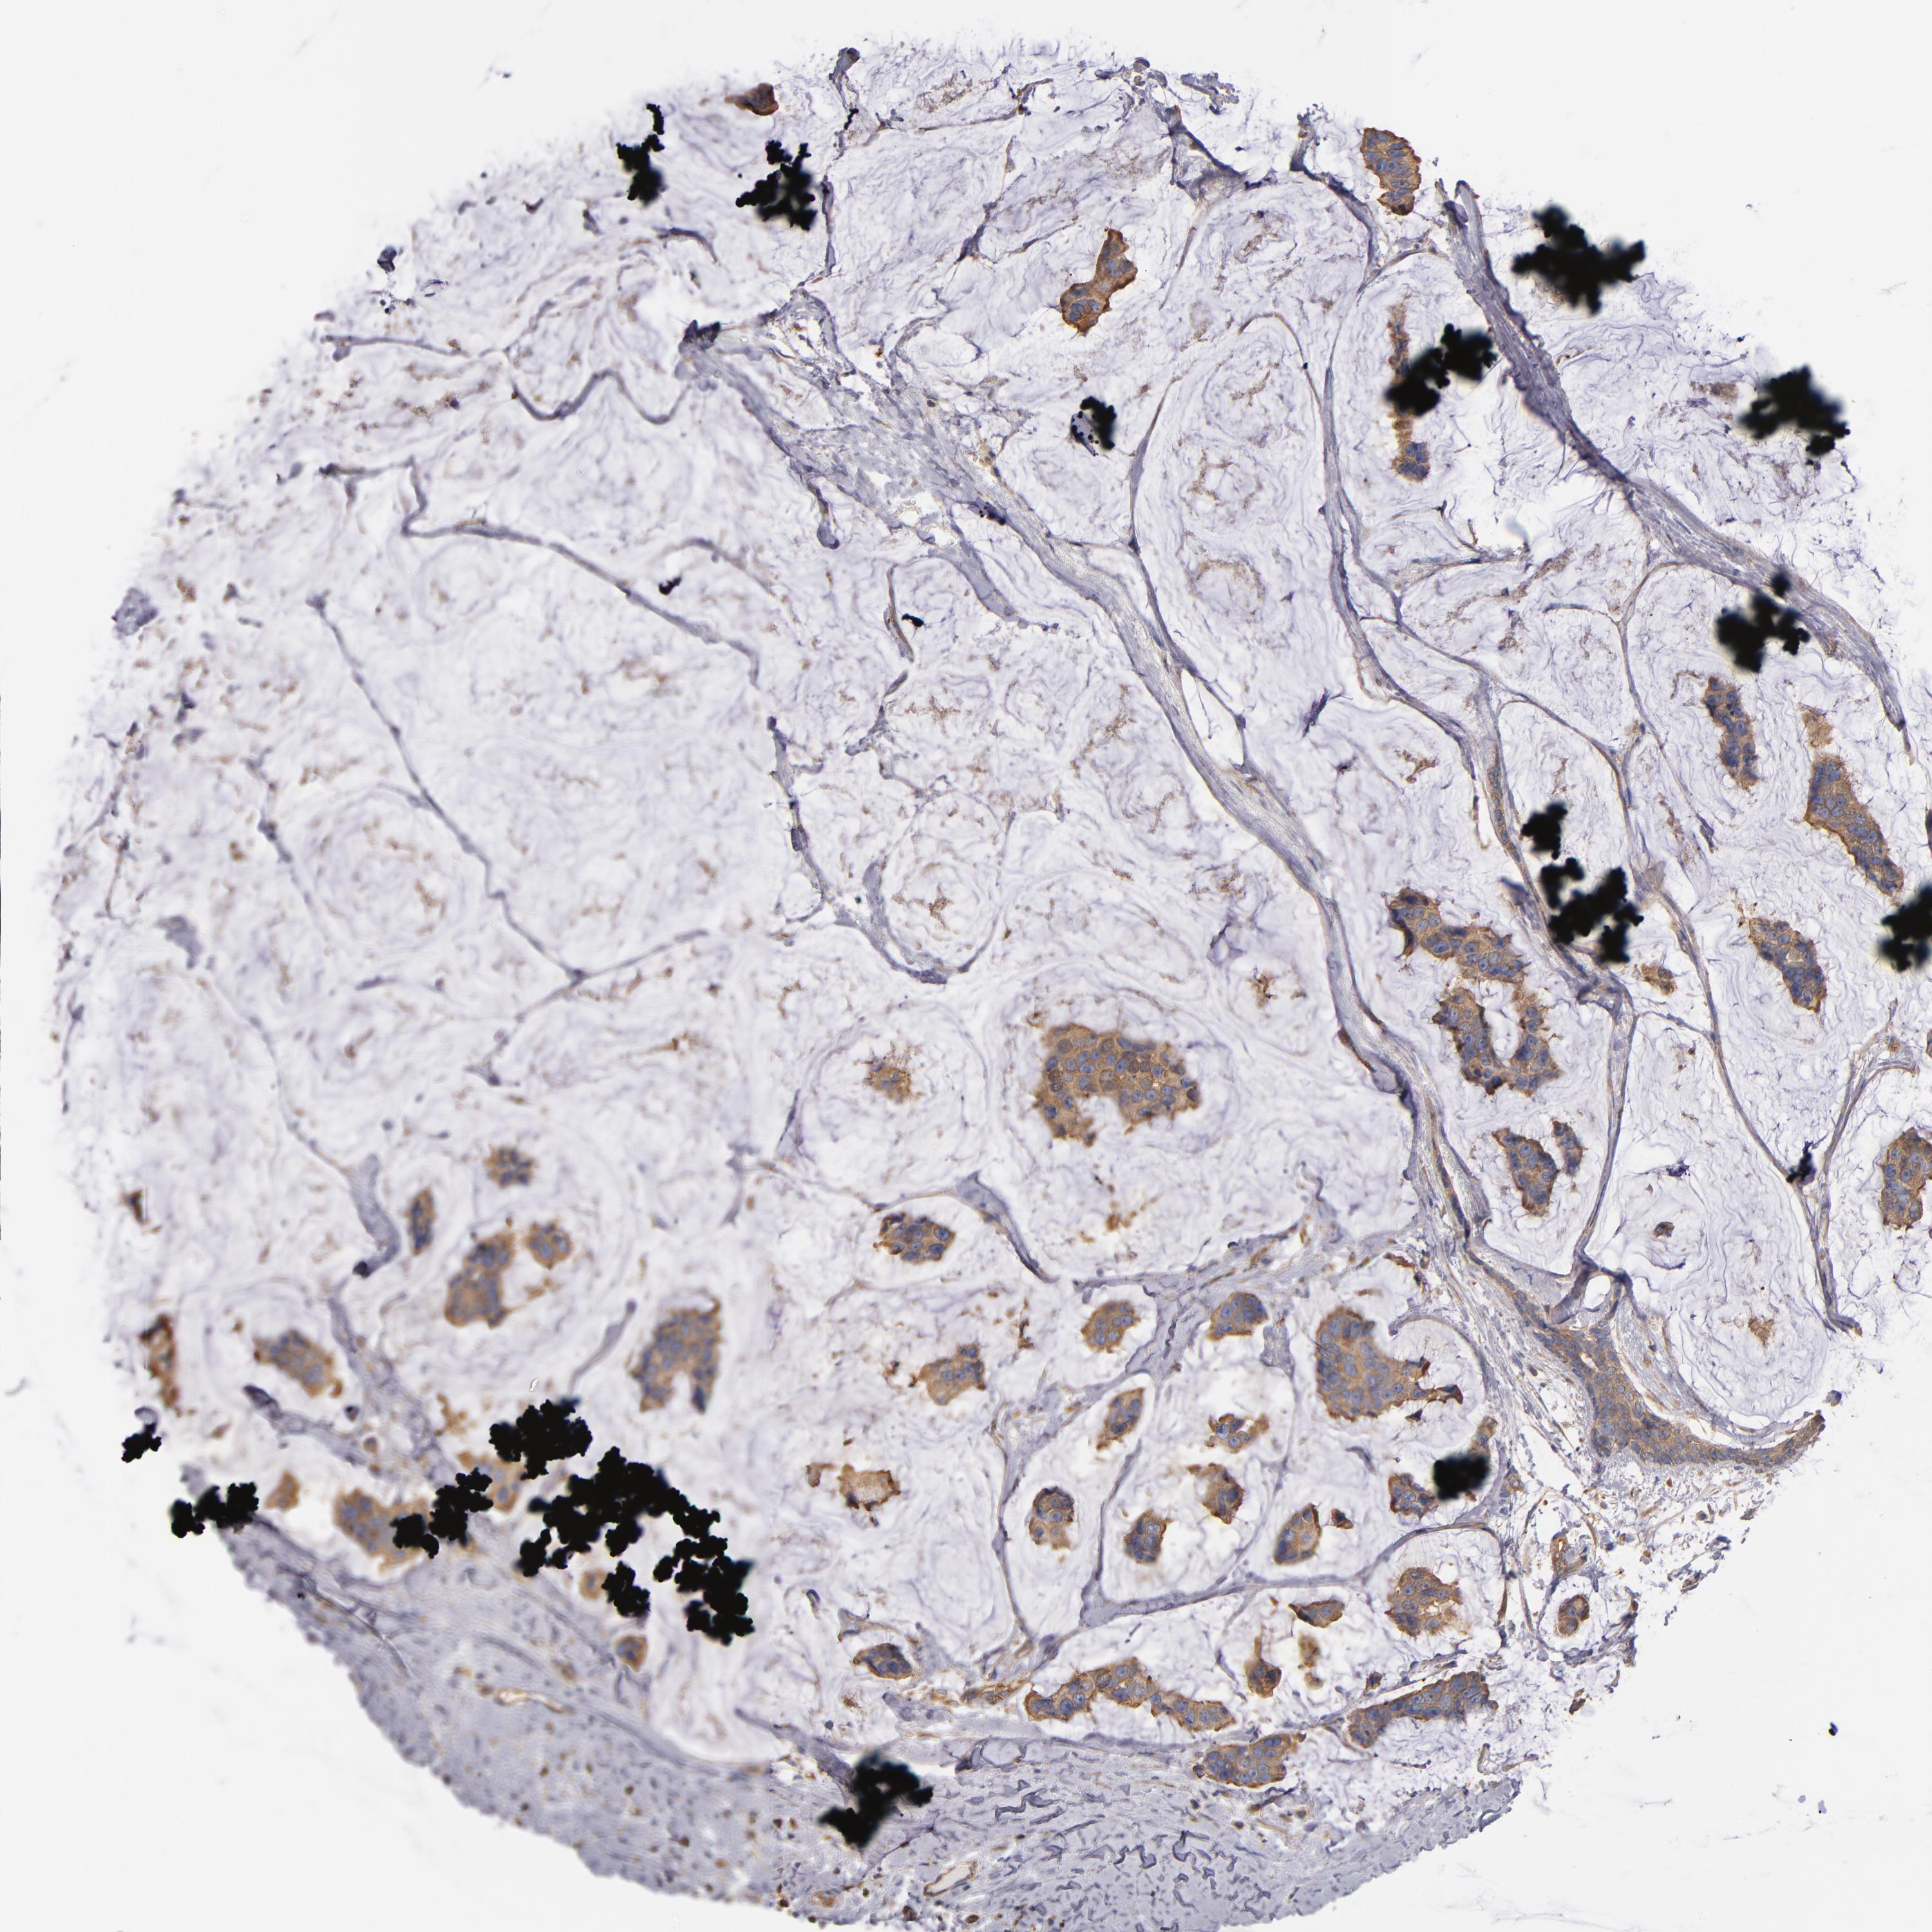

BRCA TCGA BRCA VALIDATION PROTEIN EXPRESSION

ANTIBODIES

AND

VALIDATION